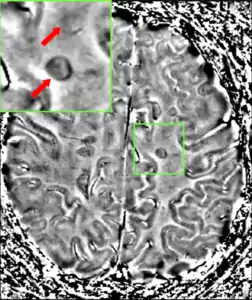

Magnetic resonance imaging (MRI) of the brain and spine may show areas of demyelination (lesions or plaques). Gadolinium can be administered intravenously as a contrast agent to highlight active plaques, and by elimination, demonstrate the existence of historical lesions not associated with symptoms at the moment of the evaluation.[82][83]

Central vein signs (CVSs) have been proposed as a good indicator of MS in comparison with other conditions causing white lesions.[84][85][86][87] One small study found fewer CVSs in older and hypertensive people.[88] Further research on CVS as a biomarker for MS is ongoing.[89]